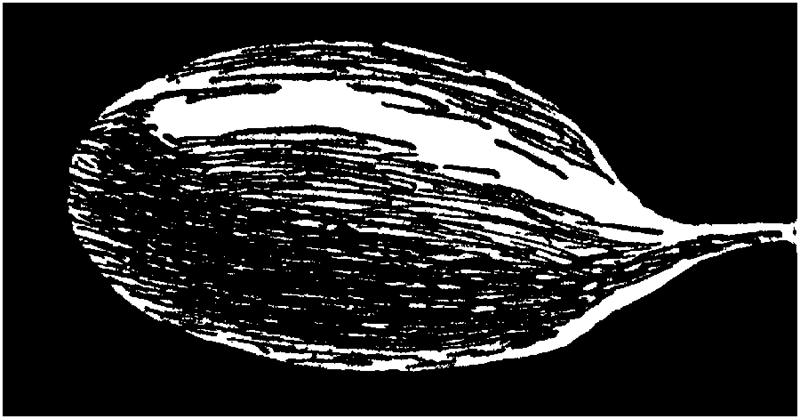

The Ovaries. The ovaries are the essential organs of reproduction. For it is they that generate the eggs, or ova, or ovules, which, after becoming fertilized or fecundated by the spermatozoa of the male, develop into children. Without the ovaries of the female, the same as without the testicles of the male (to which they correspond), no children could be begotten, and the entire human race would quickly disappear from our planet. The ovaries are two in number; they are embedded in the broad ligaments [35]which support the womb in the pelvis, one on each side of the womb. They are of a grayish or whitish pink color, and are about an inch and a half long, three-quarters of an inch wide, and one-third of an inch thick. They weigh from one-eighth to one-quarter of an ounce. Their surface is either smooth or rough and puckered. Think of a large blanched almond and you will have a pretty fair idea of the size and shape of an ovary.

Ovary.